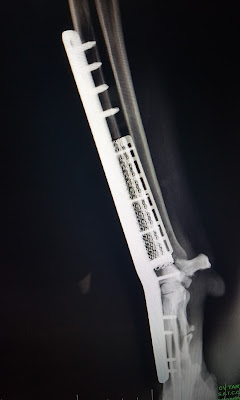

Realizamos amputacion parcial del hueso, y colocacion de una endoprotesis de titanio poroso fijada mediante una placa bloqueada especial de artrodesis pancarpiana.

una vez medido, realizamos amputación y colocación de la endoprótesis que fijaremos con la placa especial a medida para este caso

Si las imagenes radiologicas postquirurgicas son impresionantes, mas aun es la evolución del paciente